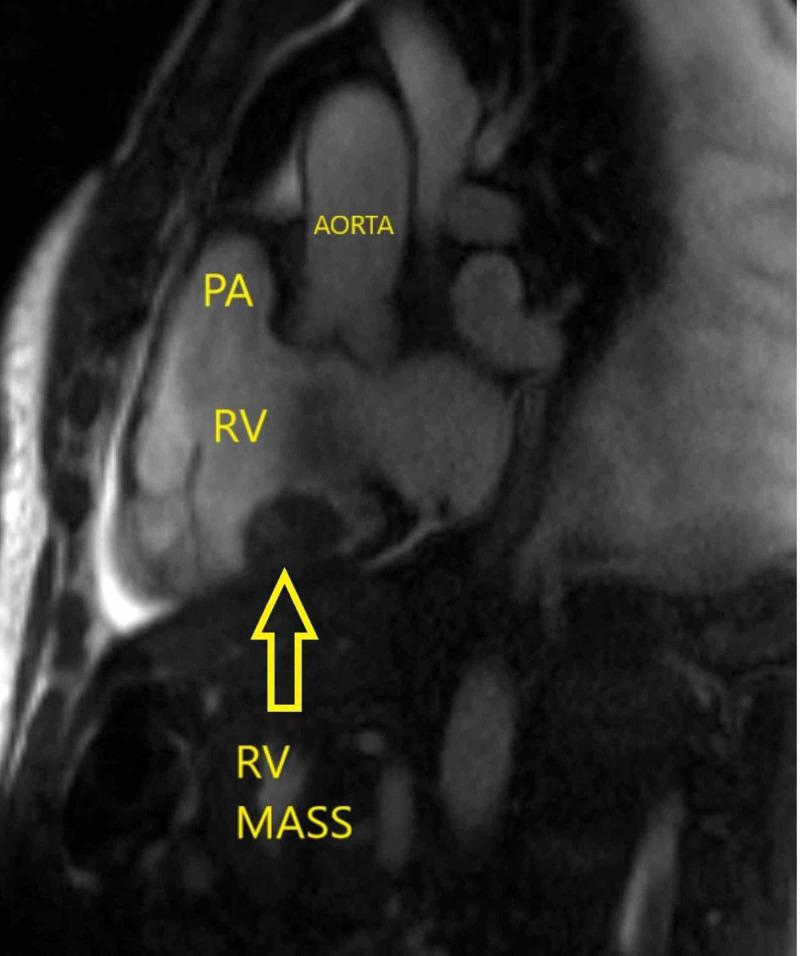

感染性右心室血栓作为持续性脓毒症的一个病因

Infected Right Ventricle Thrombus as a Cause of Persistent Sepsis.

The presentation of fevers in a patient with active intravenous (IV) drug use is often challenging, as there is a wide range of both infectious and noninfectious disorders that can cause fevers. A thorough diagnostic workup is essential in identifying the etiology of these fevers. We report a rare case of an infected right ventricular (RV) thrombus as a cause of persistent fever and sepsis in a 46-year-old patient with IV drug use. The patient continued to have persistent bacteremia inspite of appropriate IV antibiotics. Hence, the patient warranted a cardiothoracic surgical excision of the infected RV thrombus following which the patient showed remarkable improvement.

对于有静脉注射毒品史的患者,发热的表现往往具有挑战性,因为有多种感染性和非感染性疾病都可能导致发热。进行全面的诊断检查对于确定这些发热的病因至关重要。我们报告了一例罕见病例,一名46岁有静脉注射毒品史的患者,因右心室(RV)血栓感染导致持续发热和败血症。尽管使用了合适的静脉抗生素,患者仍持续存在菌血症。因此,该患者需要进行心胸外科手术切除感染的右心室血栓,术后患者有显著改善。